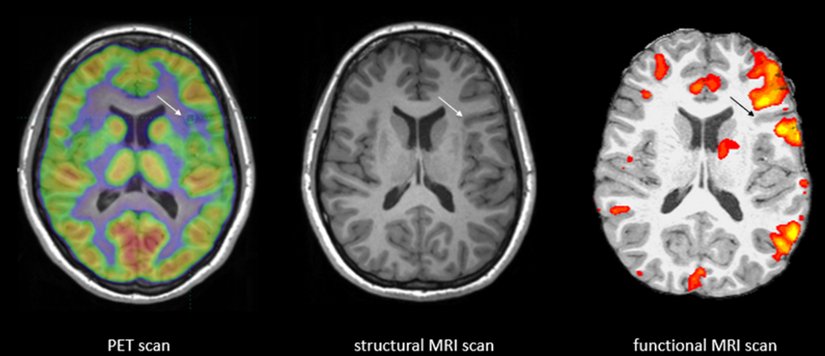

Bilinç öncesi sürecin nörolojik temellerini anlamak, bilişsel sinirbilimde çok önemli bir noktayı oluşturmaktadır. Çeşitli beyin yapıları ve ağları arasındaki karmaşık etkileşim, bilginin bilinçdışından bilinçli durumlara geçişini düzenleyerek bilinç öncesi bilişin dinamik manzarasını şekillendirir. Fonksiyonel nörogörüntüleme çalışmaları, özellikle fMRI ve EEG gibi teknikleri kullananlar; bilinç öncesi işlemlerle ilişkili sinirsel alt katmanların tanımlanmasına önemli ölçüde katkıda bulunmuştur.

Nörogörüntüleme tekniklerindeki ilerlemeler, bilinç öncesi fenomenleri incelemek için deneysel birikime önemli ölçüde katkıda bulunmuştur. Fonksiyonel manyetik rezonans görüntüleme (fMRI), araştırmacıların bilinç öncesi süreçlerin sinirsel bağıntılarını yüksek uzaysal çözünürükle incelemesine olanak tanır. Örneğin, bilinçaltı duygusal uyaranları araştıran çalışmalar, bilinçli farkındalığın yokluğunda bile amigdala aktivasyonunun arttığını bildirmektedir. Nörogörüntülemenin kullanımı, bilinç öncesi bilişte yer alan belirli beyin bölgelerinin tanımlanmasını mümkün kılarak ilgili sinirsel substratların ayrıntılı anatomilerinin anlaşılmasını sağlamaktadır.